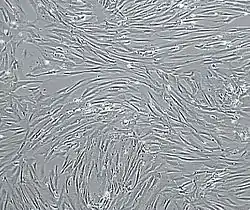

![]() Vascular smooth muscle cells, isolated from human aorta, growing and forming a monolayer in cell culture. | |